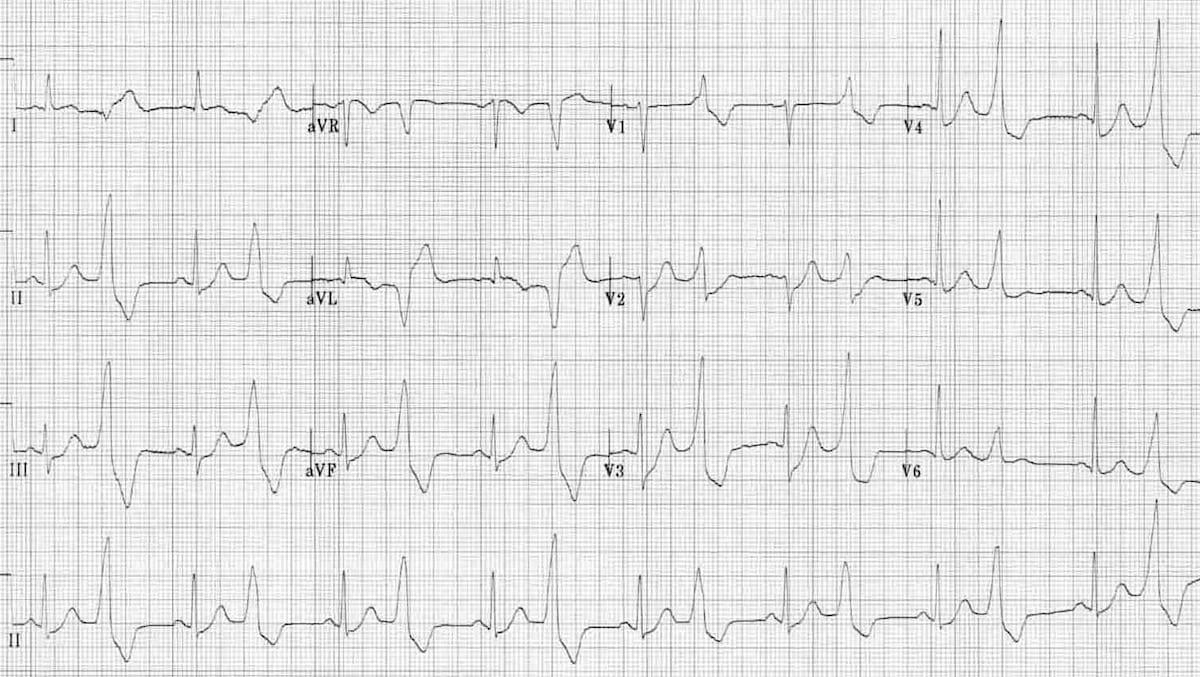

Antero-lateral STEMI

ST elevation can be clearly seen in V2-V4 and V5, V6, I, and aVL. This corresponds to the myocardial territory of the anterior and lateral wall.

© Life in the Fast Lane. Licensed under CC BY-NC 4.0

Inferior STEMI

ST elevation can be clearly seen in leads II, III, aVF. This corresponds to the myocardial territory of the inferior wall.

https://litfl.com/inferior-myocardial-infarction-ecg-library/

© Life in the Fast Lane. Licensed under CC BY-NC 4.0